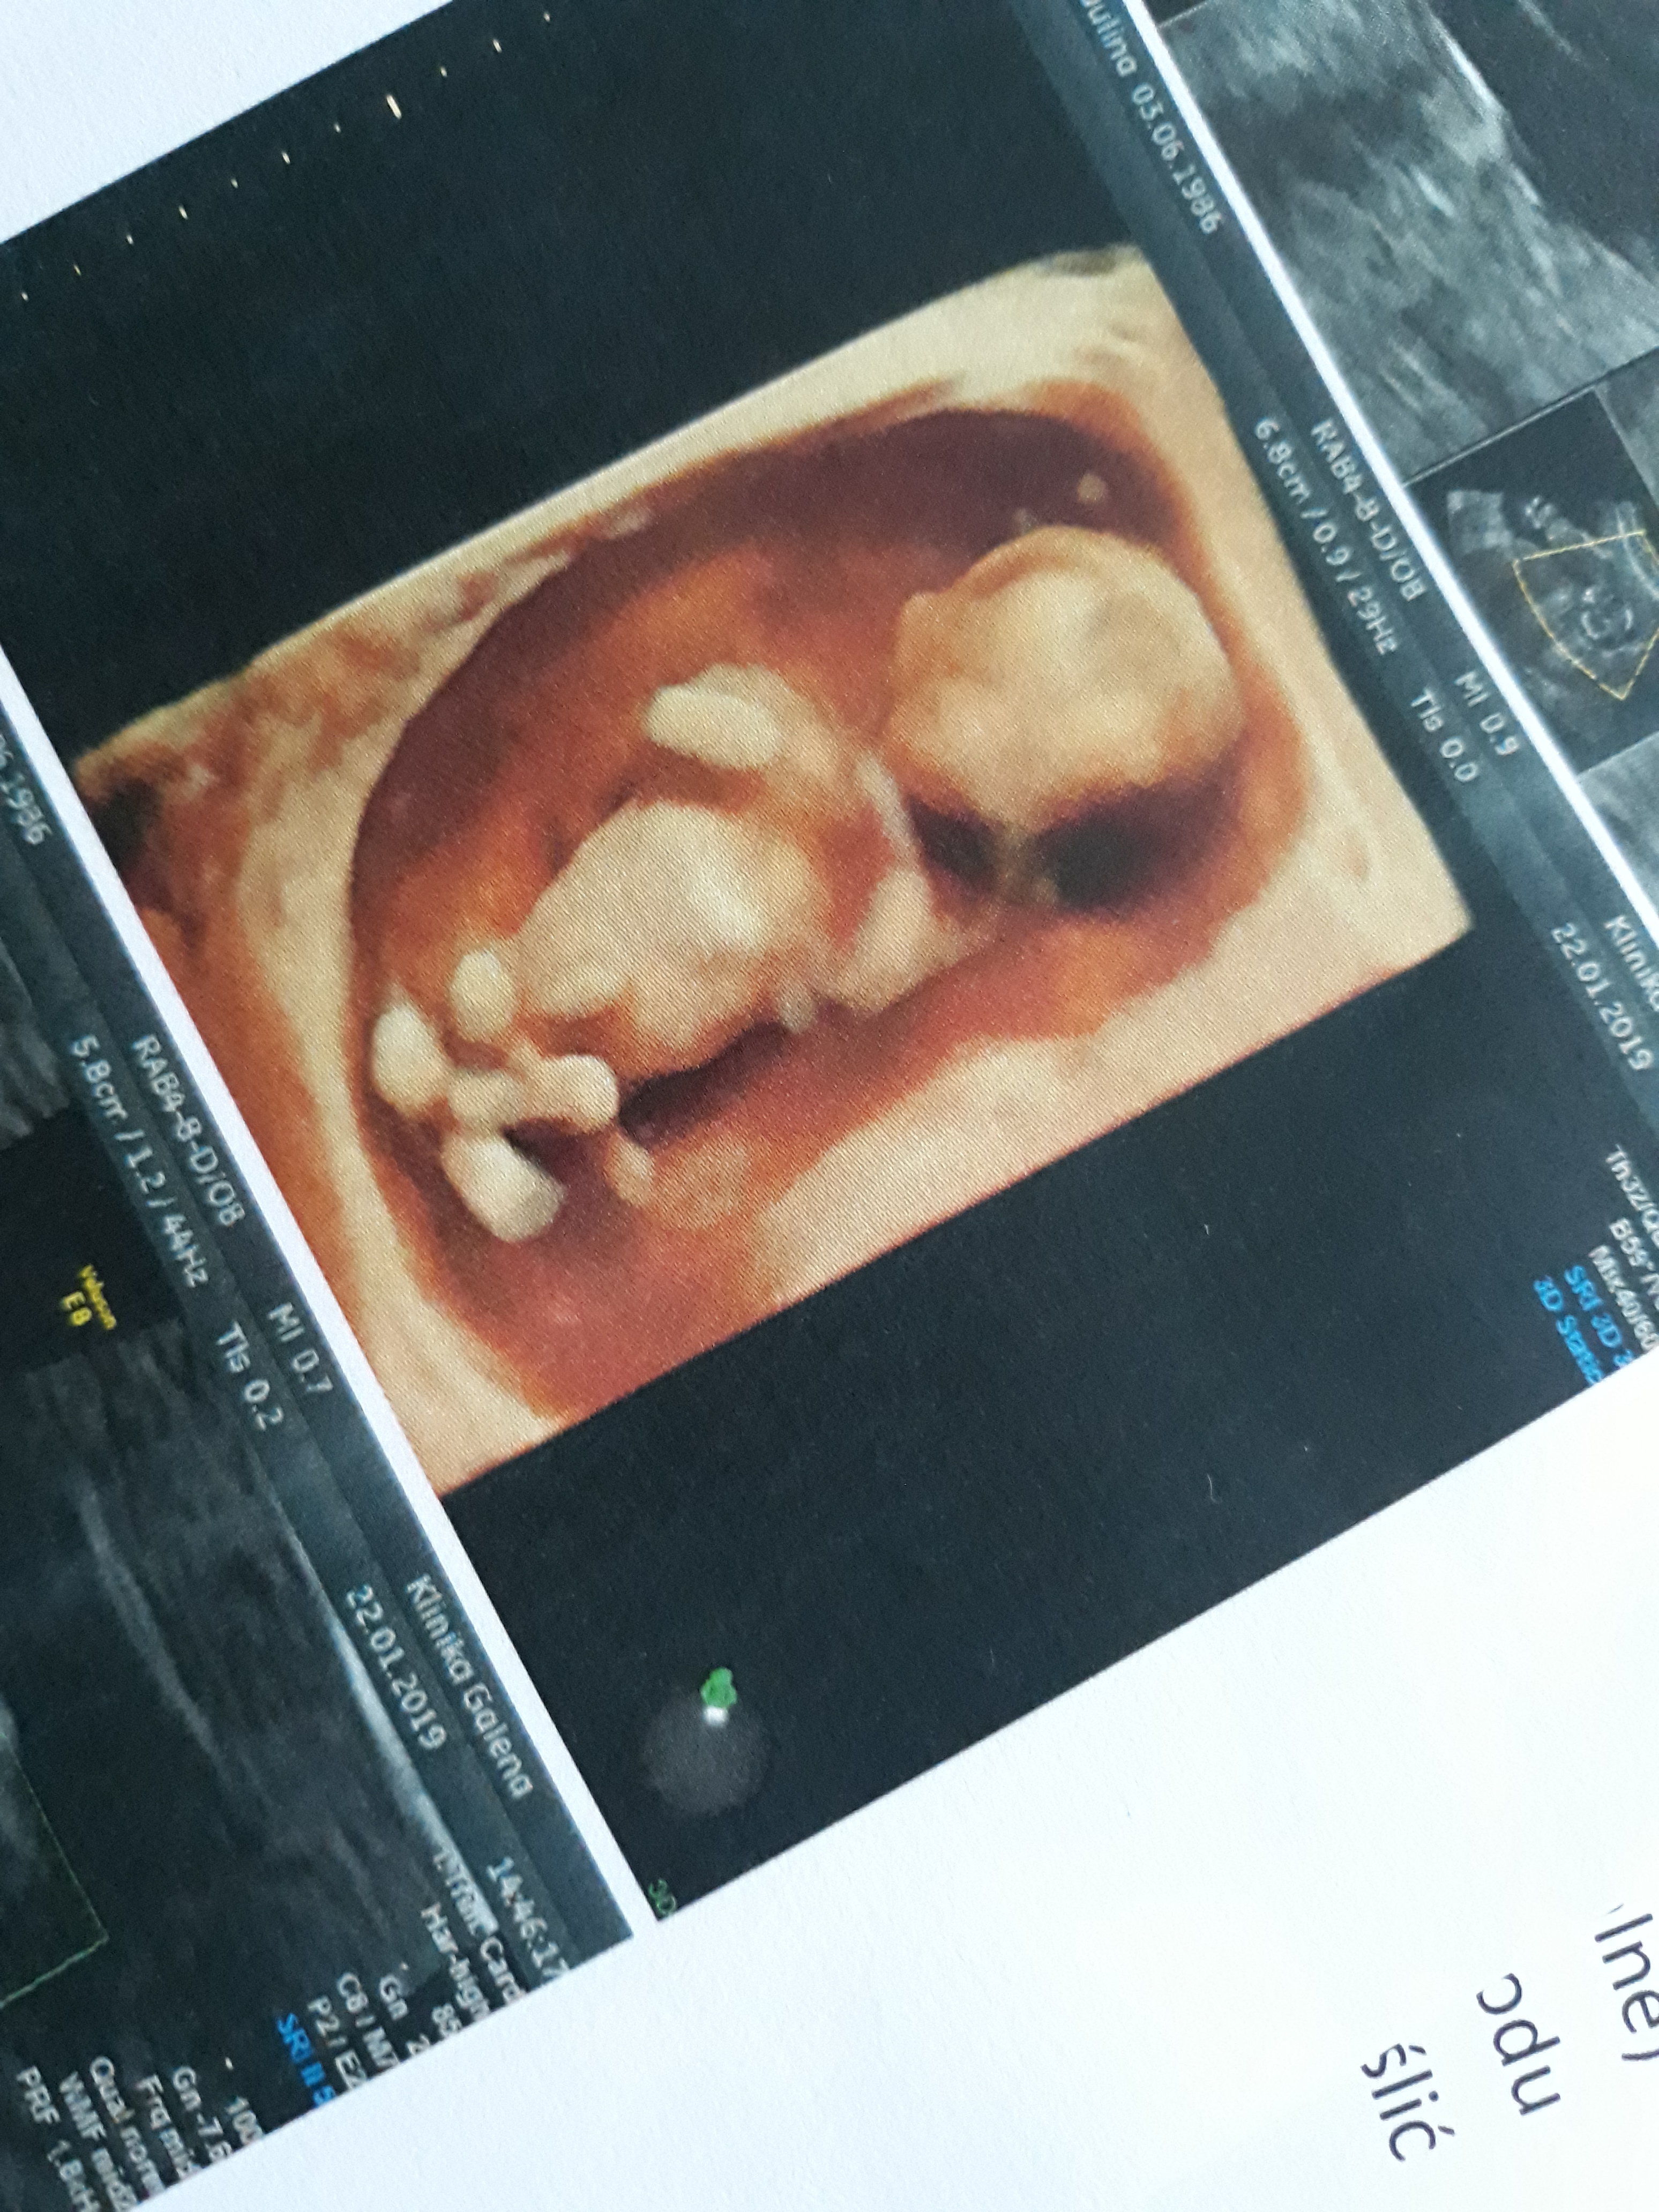

U mnie wizyta w środę, a poniżej wrzucam zdjęcie z wtorkowych badań

Zobacz załącznik 937679